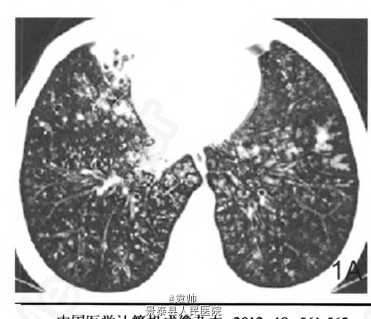

查体——体温38℃,呼吸25次/分,脉搏85次/分,血压120/80mmHg;咽部充血,扁桃体不大;双肺呼吸音清晰,双肺可闻及断续性湿罗音,未闻及哮鸣音及胸膜摩擦音;心界不大,心率85次/分,心律齐,各瓣膜听诊区未闻及杂音。余查体无明显异常。 辅查——肺CT示:两肺多发小结节、颗粒状影,弥漫性支气管壁增厚伴扩张,部分呈迂曲管状、环状及囊状改变,局部病灶呈“印戒征”,肺外带呈“树牙征”,并可见散在小斑片状密度增高模糊影;两肺门未见异常,纵隔内未见异常肿大淋巴结(图1A,B)。血常规提示白细胞轻度升高。余检验检查无特殊。

4个月后症状明显好转,复查肺部CT:双肺部结节状阴影明显减少(图1B)。弥漫性泛细支气管炎(diffuse panbronchiolitis,DPB)是一种弥漫存在于两肺呼吸性细支气管的气道慢性炎症,受累部位主要是呼吸性细支气管以远的终末气道。由于炎症病变弥漫性地分布并累及呼吸性细支气管壁的全层,故称为DPB。临床上多表现为咳嗽、咳痰和运动后气促,可表现为慢性鼻窦炎和慢性支气管炎,严重者可导致呼吸功能障碍。DPB在我国不常见,其发病率较低,故目前误诊率较高,易被误诊为支气管扩张、慢性支气管炎或肺间质纤维化等疾病。目前本病在国际上尚无统一的诊断标准,我国主要参考日本1998年第二次修订的临床诊断标准,诊断项目包括必须项目和参考项目。必须项目:①持续咳嗽、咳痰及活动时呼吸困难;②合并有慢性副鼻窦炎或有既往史;③胸部x线平片见两肺弥漫性散在分布的颗粒样结节状阴影或胸部CT见两肺弥漫性小叶中心性颗粒样结节状阴影。参考项目:①胸部听诊断续性湿罗音;②1 s用力呼气容积占预计值百分比(FEVl占预计值%)70%以及低氧血症(PaO2,<80mmHg);③血清冷凝集试验效价增高(1:64以上)。确诊需符合全部必须项目及参考项目中的2项以上。可疑诊断需符合必须项目1和2。如能早期诊断,早期治疗,DPB是可以治愈的。【摘自:《中国医学计算机成像杂志》2012,18:561-562《弥漫性泛细支气管炎1例病例报道及文献复习》】